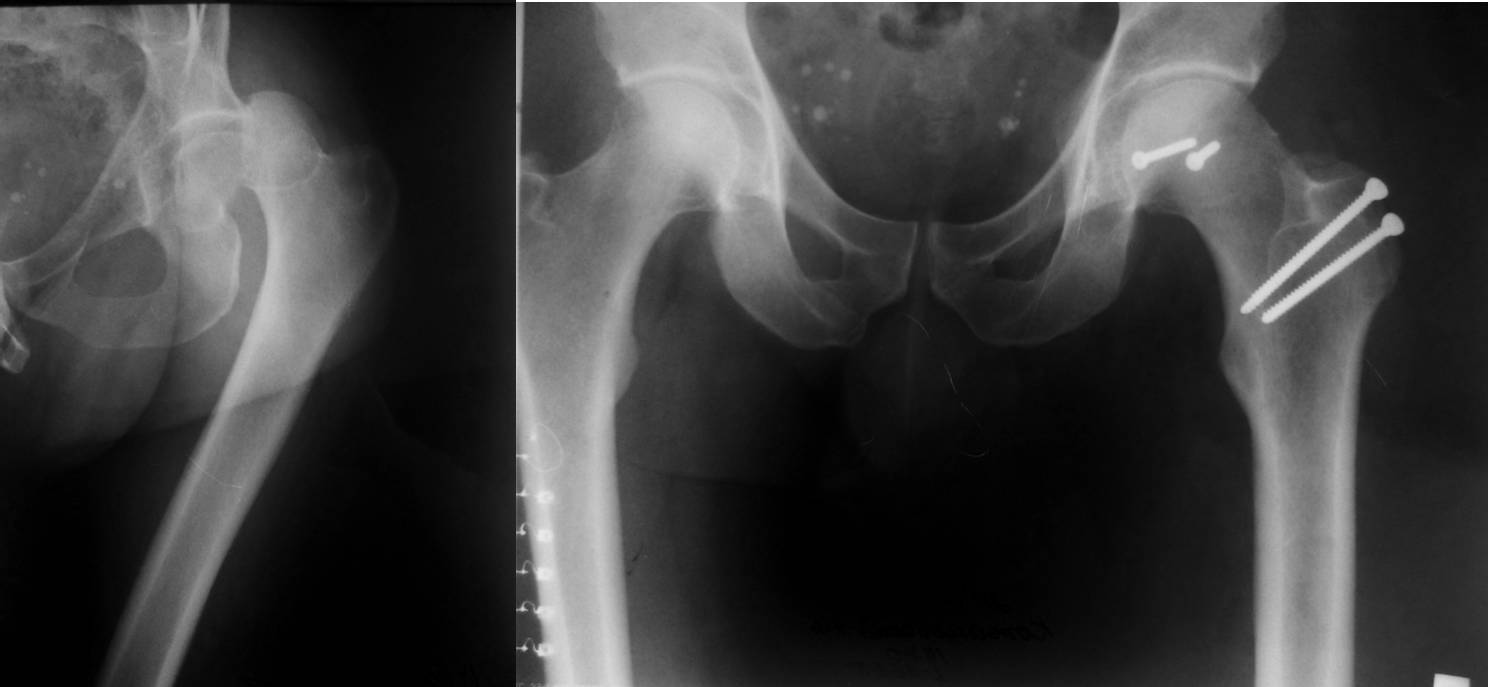

Поскольку имеется перелом края вертлужной впадины, перелом относится к

типу Pipkin IV. Ну, это так, к слову. Больной до шестидесяти лет,

поэтому методом выбора должна быть открытая репозиция перелома,

остеосинтез винтами. Головки винтов должны быть заглублены ниже уровня

суставного хряща. Нет на представленной КТ срезов в корональной

плоскости, поэтому невозможно точно определить имеющийся дефект

задневерхнего края вертлужной впадины и, следовательно, необходимость

репозиции и фиксации её отломанного фрагмента. Лучшим доступом в данном

случае является латеральный доступ с отсечением большого вертела по Ganz

с вывихом головки бедренной кости в рану. Доступ позволяет не только

без проблем выполнить репозицию и фиксацию не только перелома головки

бедренной кости,  но и края вертлужной впадины в случае необходимости.

Доступ подробно описан в«Rockwood And Green's Fractures In Adults». Один

случай из личного опыта, когда использовался этот доступ–  во вложенном

файле.